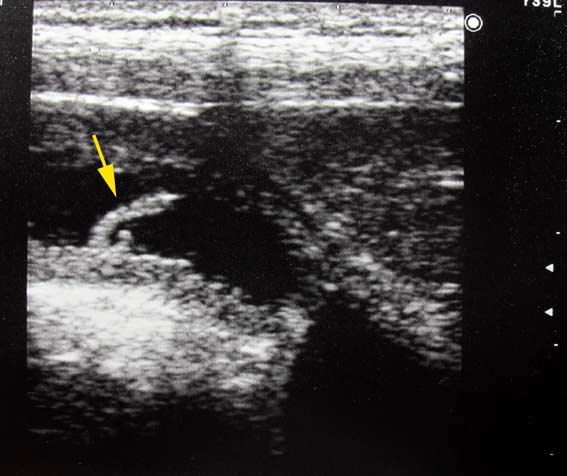

Ученик 10 класса с жалобами на перидические боли в эпигастрии, из гастроэнтерологического отделения.

При УЗИ желчный пузырь с равномерным утолщением стенок, в просвете - акустически прозрачная желчь, имеется какое-то образование не более 10мм длиной, фиксированное к стенке пузыря и, как нам с коллегой показалось, совершающее самостоятельные движения своей свободной частью.

Сонограмма желчного пузыря, линейный датчик 7.5 МГц

Мы предположили паразита, вероятнее всего острицу, и ... были осмеяны коллегами.

Пациент появился через месяц, после выпускных празднеств, эта штука уже свободно плавала в просвете пузыря, вероятно не вынесла выпуского. Пузырь был удален в хирургическом отделении, никаких дополнительных структур визуально не было обнаружено (хотя я не уверен, что пузырь был осмотрен внимательно). На гистологии - хронический эозинофильный (!- СК) холецистит.